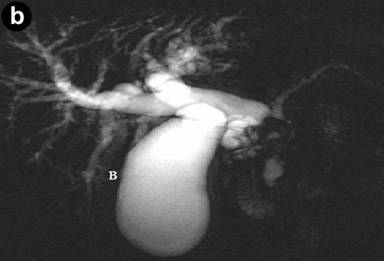

The patient then developed painless obstructive jaundice four months after the procedure. As the clinical features changed and became more sinister, CT scan was repeated, following which a referral was made to the tertiary regional HPB unit. The pre-bypass CT had shown inflammation in the groove with cystic changes in the duodenal wall. A repeat CT at our centre showed a major difference in that there was significant dilatation of the bile duct with a stenosis at the cystic duct insertion site, but the pancreatic duct was not significantly dilated. This was followed by a failed ERCP due to duodenal stenosis hence percutaneous transhepatic cholangiogram and biliary drainage was carried out. MRCP showed a small non enhancing area of low T1 signal within the pancreatic head surrounding the intra-pancreatic common bile duct extending to the ampulla of uncertain significance. CT and MRI scans revealed deleted a soft tissue mass in the head of the pancreas, abutting his superior mesenteric vein (Figures 1 and 2).

|

Figure 2. Pre-operative MRCP. a. Coronal MRCP images illustrating soft tissue mass in head of pancreas and dilatation of the intra and extrahepatic biliary tree. b. Coronal MRCP illustrating intra and extrahepatic biliary duct dilatation. |